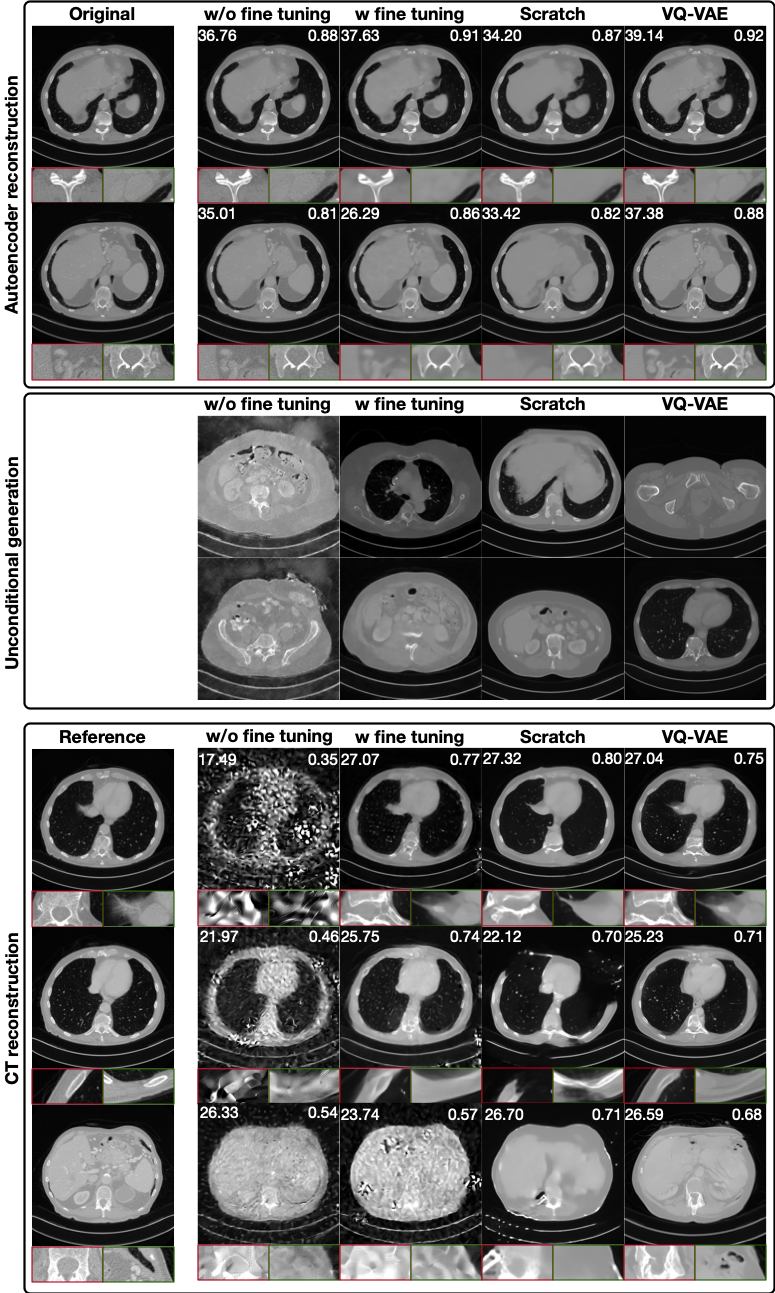

Fine Tuning Existing Natural Image Encoders (SDXL)

Comparison of autoencoder reconstruction, unconditional diffusion generation, and CT reconstruction across different autoencoders. The VQ-VAE used in our benchmark produces consistently superior representations and reconstructions, while SDXL AutoencoderKL variants exhibit reduced stability and quality.